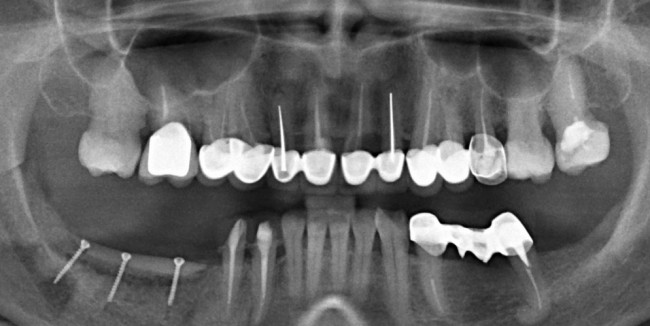

Остеопластика — всего одна операция.